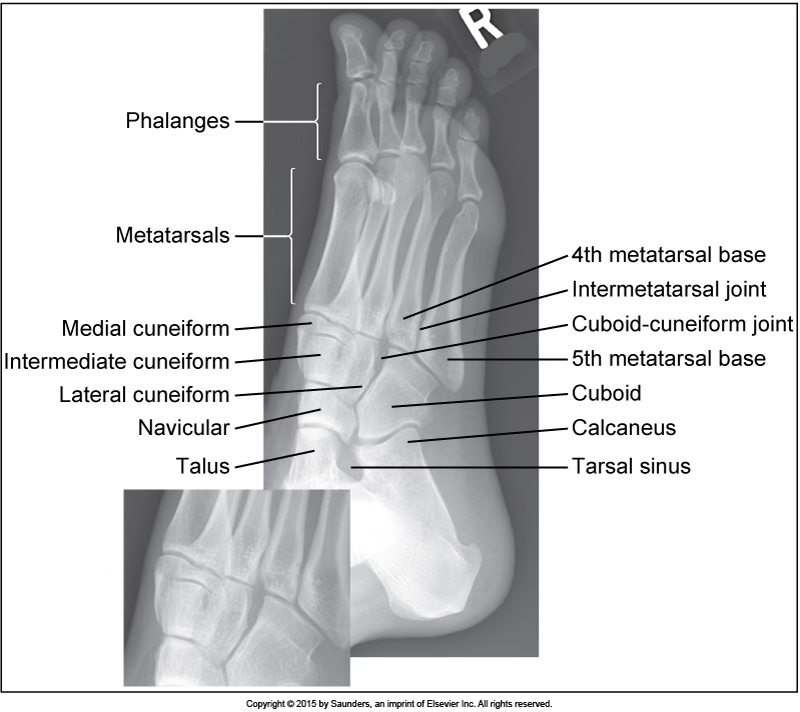

AP oblique foot

accurate positioning